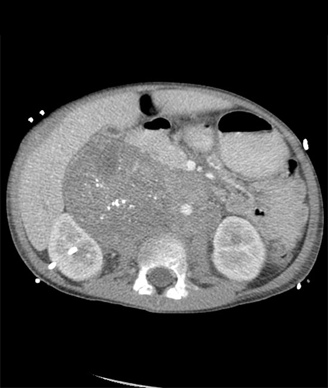

Neuroblastoma, CT of the abdomen; source: radswiki.net